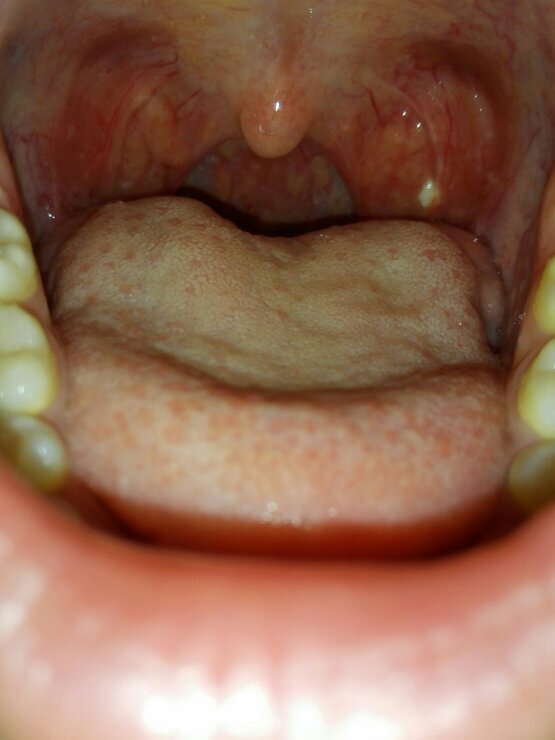

前几天吞咽有点疼痛,看到口腔内壁有个白点,不痛,就是有点膈应.

请问口腔内壁上那些突起肿块是什么看的话

然后肉都有点翻起来,还有就是上面的口腔内壁感觉多长了块肉一样不痛

求口腔科专家解答这是什么情况.谢谢